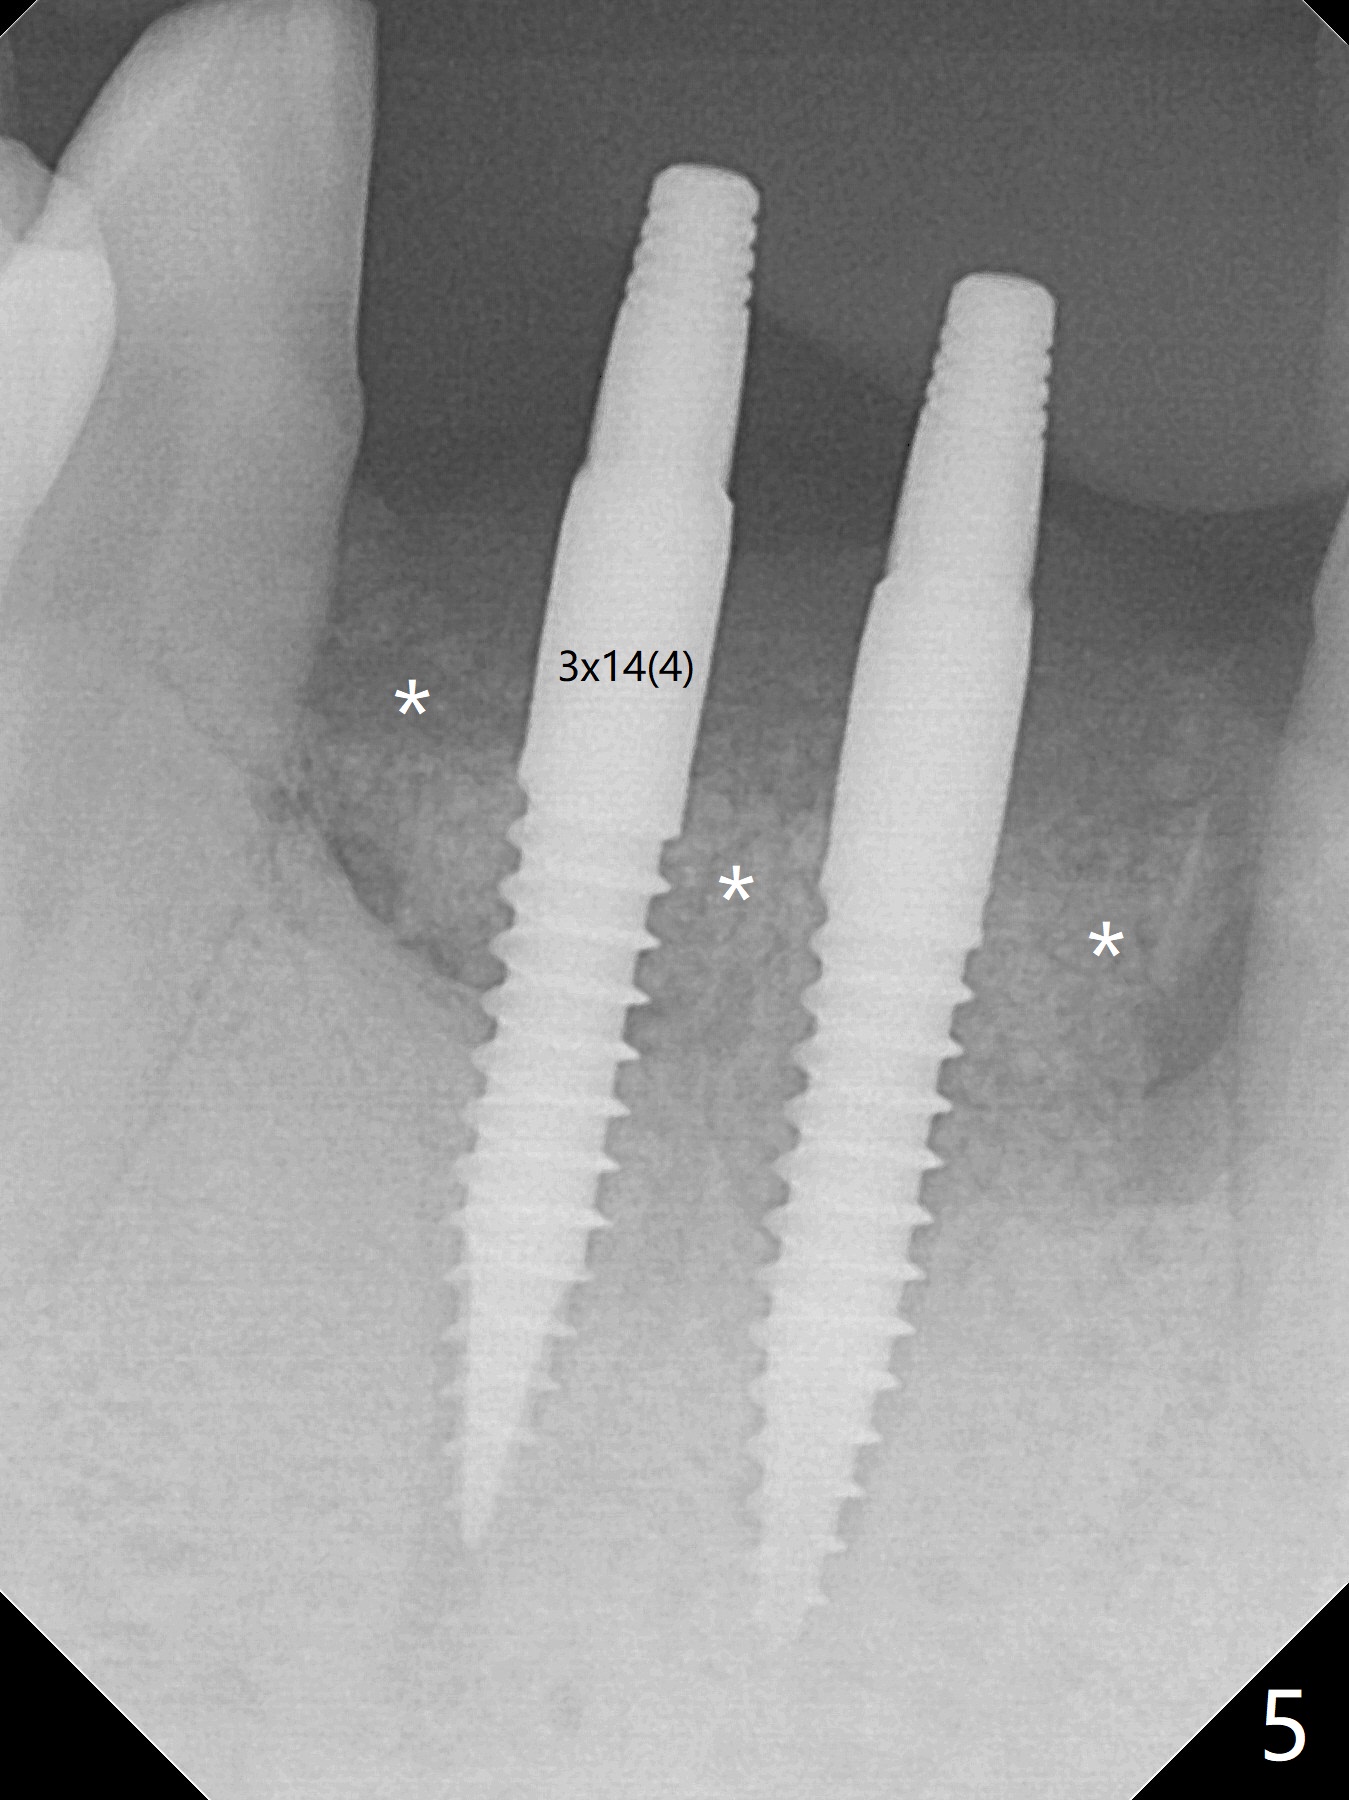

When the patient (smoker) returns for treatment, the apical abscess associated with #25 and 26 reduces with oral Amoxicillin. He agrees with 4 incisor extraction because of 2 apical fistulae (Fig.1 >). Osteotomy starts at the central incisor sockets due to mesial root exposure of the canines (Fig.2 arrowheads) and buccal alveolar bone fracture between #23 and 24 (Fig.7). Two of 3x14(4) mm 1-piece implants are placed with ~ 2 mm buccal gap (Fig.3). After Vanilla graft is placed in the bony defects (Fig.5 *) and Osteogen plug, sutures are placed (Fig.4). The implants are then placed deep to decrease thread exposure (Fig.6). Periodontal dressing is applied instead of provisional. Alveolar bone fracture between #23 and #24 accounts for why an implant is less suitably placed at #24 (Fig.7). Three months postop, composite is added to the pontic areas of the provisional (Fig.8 *). When the provisional is seated, the convex pontics press the used-to-be-flat gingiva (Fig.9 arrows). Thus the concave gingiva forms (Fig.10 *) with corresponding papillae (^). In fact the photos of Fig.8-10 is taken ~3 weeks later. Most of the grafted bone remains in place 3.5 months postop (Fig.11). A piece of floss with 2 knots in one end is placed between the middle units of the final bridge before cementation (Fig.12 (4 months 10 days postop)). In fact removal of residual cement is not so simple. It is tedious (Fig.13,14). An asymptomatic buccal fenetration with implant thread exposure is found 2 months post cementation and persists for another month in spite of advice to reduce smoking (1/2 ppd) and use of water pik (Fig.15). The area will be debrided, followed by bone graft and PRF in a month.